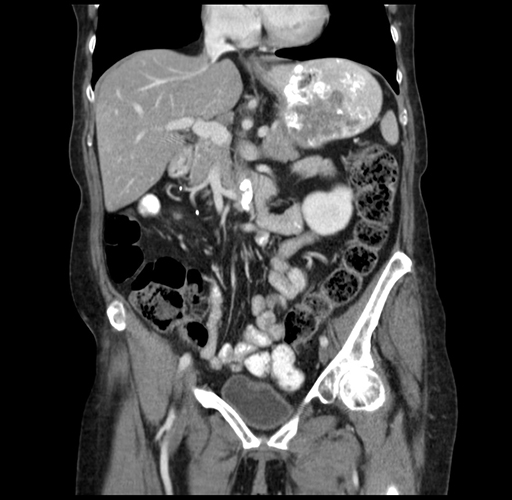

Pre-Chemo: Coronal Venous

Coronal Venous